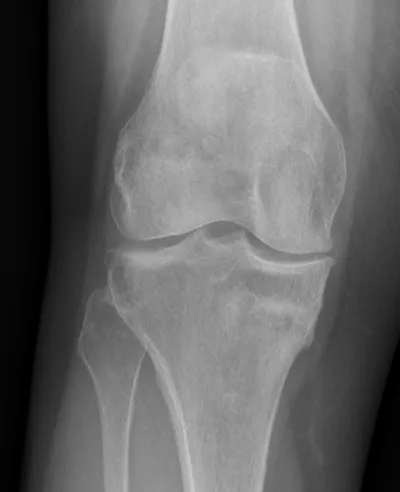

Stress fracture Radiology Images

Browse 4 medical images tagged with stress fracture. This collection includes various imaging modalities for medical education and reference.

About Stress fracture Imaging

- This collection contains 4 radiology images related to stress fracture, including various imaging modalities such as X-rays, MRIs, CT scans, and ultrasound images commonly used in medical diagnosis and education.